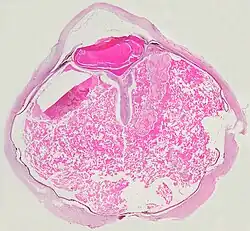

Grossly, retinal detachment and yellowish subretinal exudate containing cholesterol crystals are commonly seen.

Microscopically, the wall of retinal vessels may be thickened in some cases, while in other cases the wall may be thinned with irregular dilatation of the lumen.[11] The subretinal exudate consists of cholesterol crystals, macrophages laden with cholesterol and pigment, erythrocytes, and hemosiderin.[12] A granulomatous reaction, induced by the exudate, may be seen with the retina.[13] Portions of the retina may develop gliosis as a response to injury.